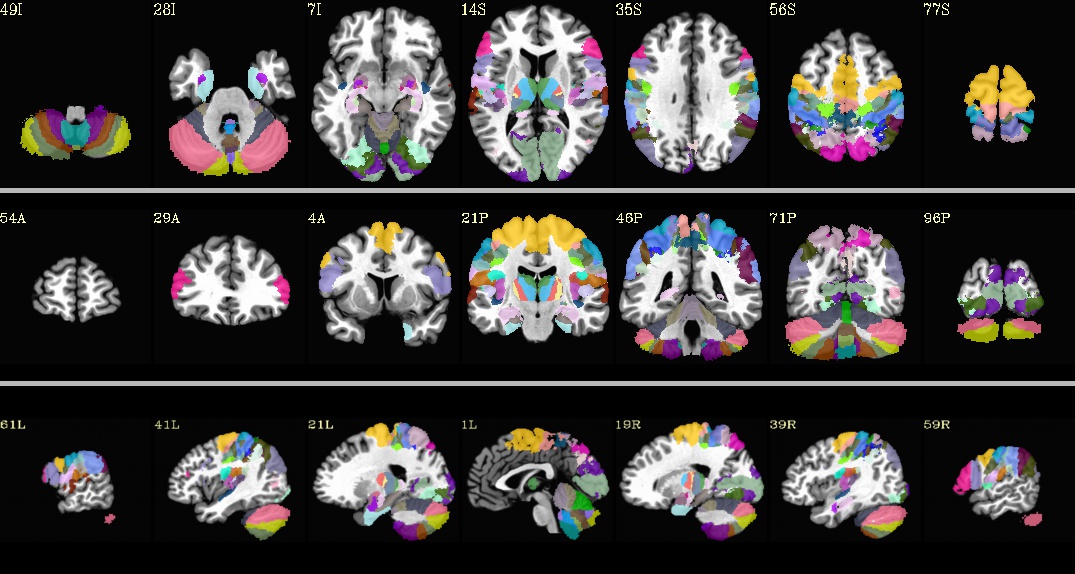

MNI_Glasser_HCP_v1.0.nii.gz¶

Underlay: MNI152_2009_template_SSW.nii.gz |

BN_Atlas_246_1mm.nii.gz¶